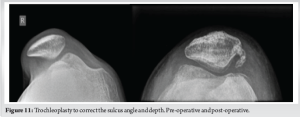

The valgus at the knee was corrected to neutral alignment (Fig. 10). The mechanical lateral distal femoral angle was corrected from 81° to 88° post-operatively. The trochleoplasty had increased the trochlear depth from 1.2 to 4 mm and the sulcus angle from 172° to 140° postoperatively (Fig. 11). The patient is currently at 1 year follow-up, and has attained full range of motion (Fig. 12). There has been no further episodes of patellar dislocation and the patient is leading an active lifestyle without apprehension or instability. The Tegner Lysholm knee score improved from a pre-operative value of 51 to a post-operative value of 94, and the Kujala knee score also showed improvement from 18 to 27 postoperatively (Fig. 13).